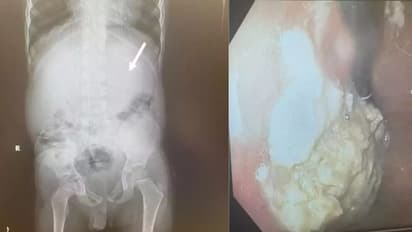

എന്തായാലും വിശദമായ സ്കാനിംഗ് പരിശോധന നിര്ബന്ധമാണെന്ന് മനസിലാക്കിയ ഡോക്ടര്മാര് ബാലനെ സ്കാനിംഗിന് വിധേയനാക്കി. ഇതോടെയാണ് ഞെട്ടിക്കുന്ന സത്യം ഇവര് മനസിലാക്കുന്നത്. കുട്ടിയുടെ ആമാശയത്തില് അട്ടിയായി ച്യൂയിങ് ഗം കിടക്കുന്നതായിരുന്നു സ്കാനിംഗില് കണ്ടത്.

സംഭവിച്ചത് എന്തെന്നാല് കുട്ടി കഴിക്കുന്ന ച്യൂയിങ് ഗമ്മുകള് പതിവായി തുപ്പിക്കളയാതെ വിഴുങ്ങുകയായിരുന്നുവത്രേ പതിവ്. ഇത് ആമാശയത്തില് പരസ്പരം ഒട്ടിപ്പിണഞ്ഞ് കെട്ടിക്കിടക്കാൻ തുടങ്ങിയതോടെയാണ് കുട്ടിക്ക് അസ്വസ്ഥതകളും വേദനയുമെല്ലാം അനുഭവപ്പെട്ട് തുടങ്ങിയത്.

യുഎസിലെ ഒഹിയോ സ്വദേശിയായ ബാലനാണ് ഇത്തരമൊരു ദുരവസ്ഥയുണ്ടായത്. അപൂര്വമായ സംഭവമായതിനാല് തന്നെ ഡോക്ടര്മാരുടെ കേസ് സ്റ്റഡി ഒരു പ്രസിദ്ധീകരണത്തിലൂടെ പുറത്തുവന്നതോടെയാണ് സംഭവം ഏവരും അറിയുന്നത്. എന്തായാലും ഏറെ പണിപ്പെട്ടാണെങ്കിലും കുട്ടിയുടെ വയറ്റിനകത്ത് നിന്ന് മുഴുവൻ ച്യൂയിങ് ഗമ്മുകളും ഡോക്ടര്മാര് പുറത്തെടുത്ത് മാറ്റി.